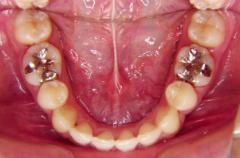

装置装着前

装置装着後